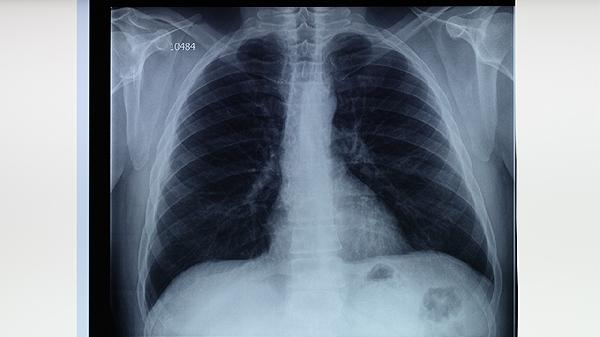

多发肺结节可通过定期随访、生活方式干预、药物治疗、手术治疗及中医调理等方式控制。多发肺结节可能与遗传因素、环境刺激、慢性炎症、既往感染、恶性肿瘤等因素有关。

定期随访是监控肺结节变化的关键措施,通过影像学检查如胸部CT扫描,能够动态观察结节的大小、形态和密度变化。对于直径小于6毫米的微小结节,通常建议每年进行一次低剂量螺旋CT检查,以评估其稳定性。随访过程中医生会记录结节的生长速度与边缘特征,帮助判断其良恶性风险。患者需严格遵循医嘱完成复查计划,避免因疏忽延误病情监测。随访期间如发现结节快速增大或出现毛刺征等可疑特征,需及时调整管理方案。